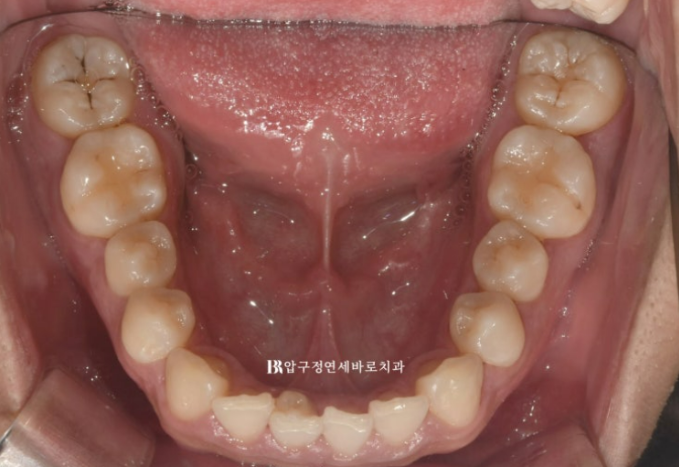

but one of the lower front teeth is crooked.

In particular, one of the lower front teeth shows an abnormal tooth shape.

The protruding part at the back is part of the tooth.

We decided to improve the tilted occlusal plane and deep bite with Invisalign Lite.

To resolve all of these issues within 14 aligners, it would be good to place one orthodontic mini-screw and use elastics as well.